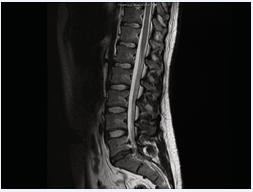

Lumbar spine magnetic resonance imaging (MRI) elicited severe spinal canal stenosis at the S1 level secondary to posterior protrusion of a degenerative L5/S1 disc (Figure1,2).

Figure 1: Sagittal T2 weighted MRI showing extruded disc (from L5/S1) causing central compression of the thecal sac at the S1 level just after the S1 nerve roots have lateralized.

There was loss of cerebrospinal fluid signal surrounding the cauda equina fibres consistent with cauda equina compression.